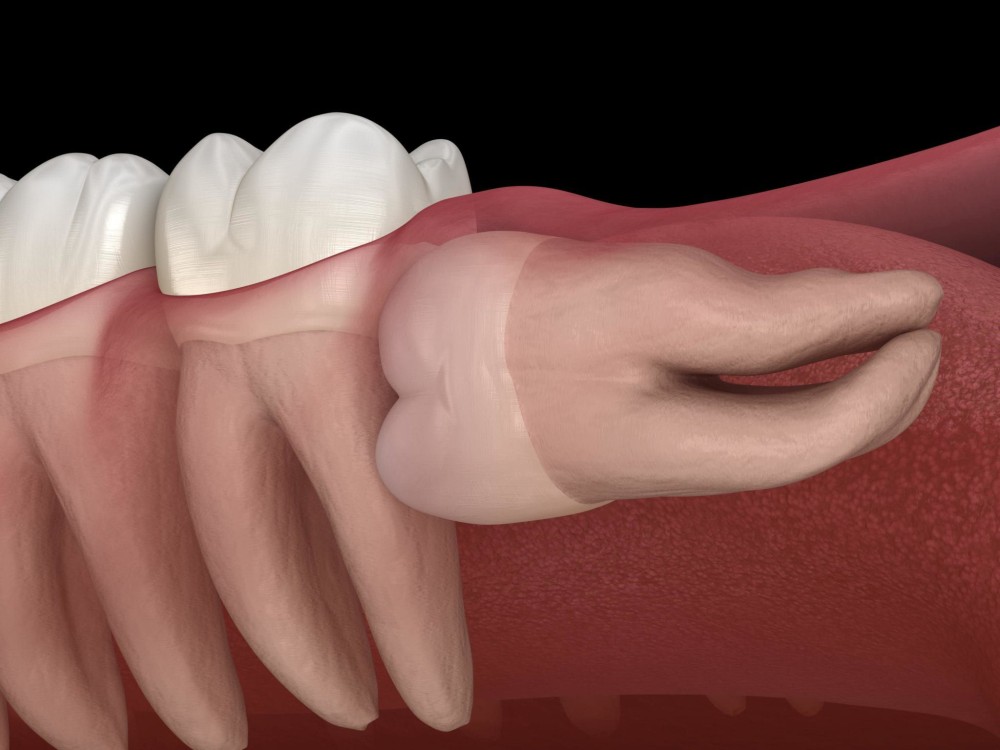

They can get partially stuck in your gums or grow at an angle. This is called an impacted wisdom tooth. Even impacted wisdom teeth don’t always need to be taken out if they aren’t causing any symptoms.

Sometimes though, the way an impacted wisdom tooth is positioned can make it easy for food and bacteria to get trapped around the gum. This can lead to swollen and sore gums (pericoronitis), tooth decay and infection. If you’re having problems such as these, your dentist may recommend taking the impacted tooth out.